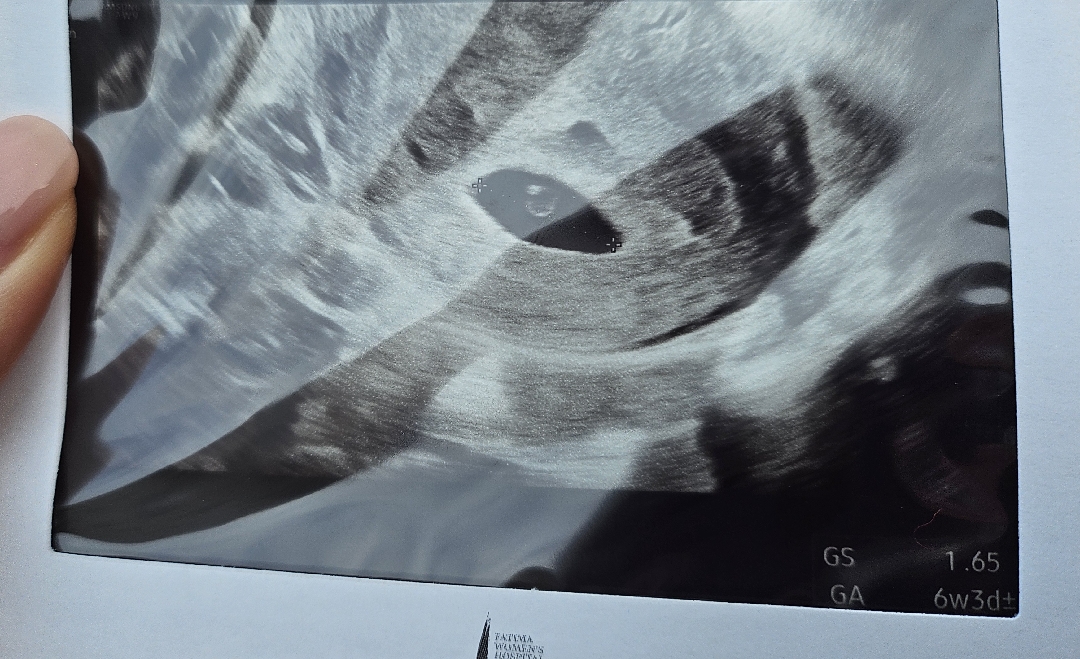

두근두근 첫 촘파

안녕하세요:) 5-6주 사이 꼬뇨맘입니다. 아침 입덧과 노곤함때매 힘들지만, 첫 초음파 보고 다음주 심소 들을 생각에 너무 행복해요ㅠㅠ 난황이 신기해서 검색해보다가 위치에 따라 아들인지 딸인지 이론이 있다며 웃기도 하고🤣 그저 건강하게만 나와줬으면 좋겠다싶어서 하루하루 설레네요ㅎㅎ 하고 싶은 일이 많지만 아이를 일찍 가지고 싶어서 28살에 결혼했는데 준비되지 않은 엄마인 것 같아 미안하면서도 아이를 위해 뭐든 할 수 있을 것 같다는 생각을 해요ㅎㅎ 여기 계신 베동님들 모두 존경스럽습니다. 👍